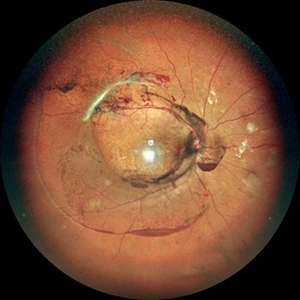

Retinoblastoma

Wide-field color fundus photograph of a 2-month old female with retinoblastoma.

Photographer: Dr. Akansha Sharma-Retina Foundation, Ahmedabad

Condition/keywords: RB gene mutation, retinoblastoma

WIDE-FIELD COLOUR FUNDUS PHOTOGRAPH OF A 2 MONTH OLD FEMALE WITH RETINOBLASTOMA